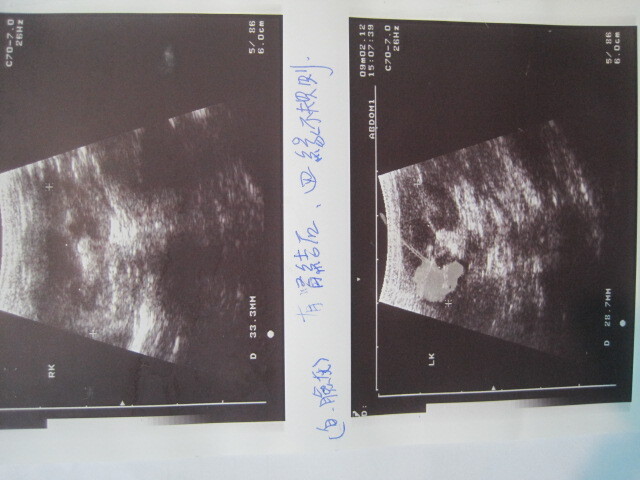

主題: 慢性拉肚子和早期腎臟病的小白金吉拉 申請者姓名: 張慧敏 花色: 申請日期: 2012-09-18 22:46:41 申請者部落格: 申請者臉書網址: 所在縣市/合作醫院: 台北市/詠欣動物醫院 治療費用: 4750元 需求人數: 11人 已結案 (2013-06-27 13:37:59) 報名人員: Kimmy Liao(已付款)、meemee(已付款)、meemee(已付款)、meemee(已付款)、Astra Liu(已付款)、A喵(已付款)、bonby(已付款)、Kenken Meow(已付款)、飛鐸(已付款)、琦(已付款)、風信子(已付款)、 候補人員: 動物病情說明: 小白近來有血便和越來越瘦 食慾不好的狀況產生.就醫發現有一顆腎臟萎縮另一顆有結石.血便的狀況 在吃藥和飲食控制下,有獲得控制.